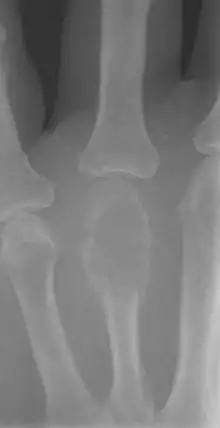

على الأشعة السينية، أورام الخلايا العملاقة (GCTs) هي الآفات التحليلية / الواضحة، التي لها موقع مشاشي وتنمو إلى السطح المفصلي للعظم المتورط.[8] إشعاعيا قد تظهر الأورام مميزة كمظهر "فقاعة الصابون".[9] وهي مميزة عن الأورام العظمية الأخرى GCTs وعادة ما يكون لها حدود حادة. تنتشر حوالي 5٪ من أورام الخلايا العملاقة عادة إلى الرئة ،[10] عندما يُشتبه في تشخيص ورم الخلايا العملاقة، قد يكون هناك حاجة إلى تصوير الصدر ب الأشعة السينية أو التصوير المقطعي المحوسب. التصوير ب الرنين المغناطيسي يمكن استخدامه أيضا.